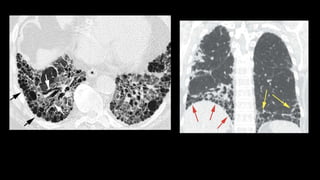

Case Profile: An 33 year old female, known case of ALL, post

BMT, presenting with new onset shortness of breath, fever,

chills and cough.

Diagnosed with Invasive aspergillosis, and

started on Voriconazole.